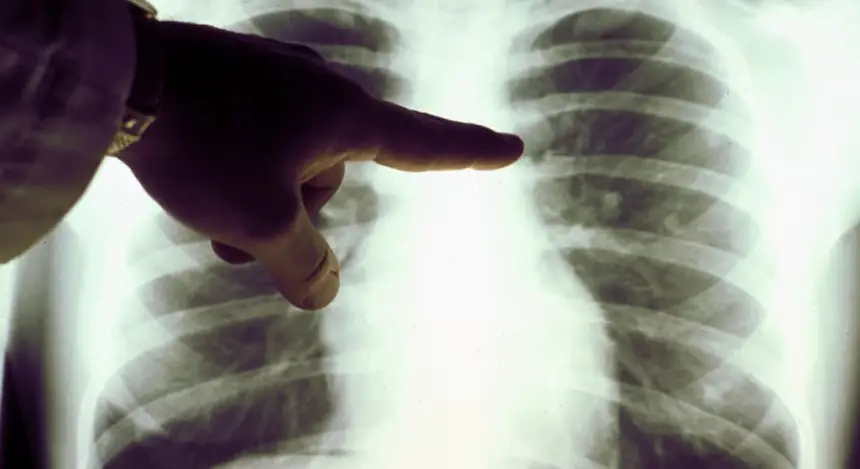

كشفت دراسة جديدة أن المرضى الذين لم يدخنوا أبدا يشكلون الآن عددا أكبر من حالات سرطان الرئة مقارنة بمن لديهم تاريخ من التدخين.

وبحسب صحيفة "ديلي ميل" البريطانية، وجد العلماء أن الشكل السائد للمرض الآن هو السرطان الغدي وهو نوع من سرطان الرئة يتكون في بطانة الأعضاء ويوجد بشكل شائع لدى غير المدخنين.

وتفوق هذا النوع على أنواع أخرى من سرطان الرئة مثل سرطان الخلايا الحرشفية وسرطان الخلايا الصغيرة التي تسببها عادة المواد الكيميائية المسببة للسرطان في السجائر، مثل القطران.